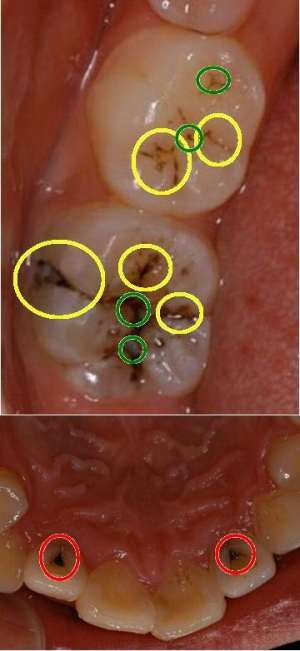

歯科のお仕事完全マニュアル 第2章 歯について STEP1 歯の構造と面│歯科スタッフ向けメディアdStyle ディースタイル。

歯の形・数・色、歯肉の色の異常 - 歯とお口のことなら何でもわかる テーマパーク8020。

特色のある歯の形態」東京錦糸町イリタニオフィス歯科用マイクロスコープ顕微鏡歯科衛生士滅菌技師YUイリタニオフィス 東京オール顕微鏡歯科治療顕微鏡専門歯科衛生士yu。

いまさら聞けない歯牙解剖Doctorbook academyドクターブックアカデミー。

もう一度学ぼう 歯牙それぞれの解剖学的特徴:小臼歯編 - Dr.HのPaper Reading。